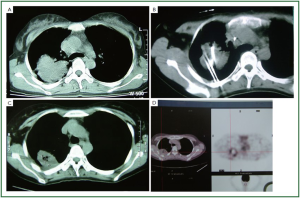

Niu and his colleagues (15) from Fuda Cancer Hospital, Guangzhou, reported the results of a total of 840 patients with non-small cell lung cancer who underwent percutaneous cryoablation in Fuda Cancer Hospital Guangzhou, China. Based on the TNM staging, there were 122 patients with stage IIa, 462 with IIb, 160 with IIIa, 64 with IIIb and 32 with IV. A total of 1,174 procedures of cryoablation were performed for 840 patients with lung cancer. There were 140 and 66 patients who underwent additional single and two sessions of cryoablation procedure, respectively, for recurrent tumors in the lungs. There were 62 patients who underwent additional session of cryoablation for liver metastases. After cryoablation, the size of the lesions increased initially, which was corresponding to the freezing margin exceeding 1 cm beyond the limit of the tumor. The cryotreated lesions then appeared shrinking or cavitated on CT images. During the follow-up, complete remission (CR) was observed in 86 patients (14.4%), partial remission (PR) in 588 patients (70.0%). However, the tumor recurred in 47.2% of the patients during a median follow-up of 34 months (range, 4 to 63 months), in the lungs, liver, brain, and bone. The recurrence at cryosite accounted 28.3% of cases. During the follow-up, the median survival of all patients was 23 months (range, 5-61 months) with 1-, 2-, 3-, 4-, and 5-year overall survival of 68%, 52%, 34%, 26% and 17%, respectively. Zhou et al. (35) in the same hospital observed therapeutic effects of cryosurgery combined iodine-125 seeds implantation in 140 patients with advanced lung cancer. However, the combination treatment did not show much better result than the whole group above mentioned. After 6 postoperative months the patients had CR of 16.8%, PR of 70.1%, stable disease (SD) of 7.4%, and progressive disease (PD) of 5.7%. The half-year and one-year survival rates were 94.3% and 65.7% respectively. Figure 2, 3 showed two patients with complete response as proven by histology.

Figure 2. The CT scan of one patient with lung cancer. A. Cancer prior to cryoablation; B. Percutaneous cryoablation under CT guidance; C. CT image 8 months after cryoablation; D. PET/CT image showed the lesion no activity 12 months after cryoablation.

Figure 3. PET/CT scan of one patient with small lung cancer. A. Cancer prior to cryoablation; B. PET/CT image 12 months after cryoablation; C. CT image showed the cavitated lesion 5 years after cryoablation; D. PET/CT image showed the lesion no activity 5 years after cryoablation.